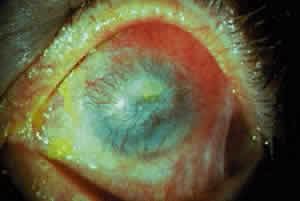

Conjunctival or corneal bullae have been described10 but are rarely observed, perhaps because they rupture readily because of the blinking action of the eyelids. Breakdown of the corneal epithelium most commonly results from entropion with trichiasis; lagophthalmos with abnormal blinking and exposure; and a diminished, unstable tear film. These erosions may become complicated by secondary bacterial infiltrates and ulcers. Predisposing factors for the development of microbial keratitis include topical corticosteroids, bandage contact lenses, trichiasis, corneal surgery, lagophthalmos, and meibomianitis.12 Corneal neovascularization may develop either as a pannus or pseudopterygium.